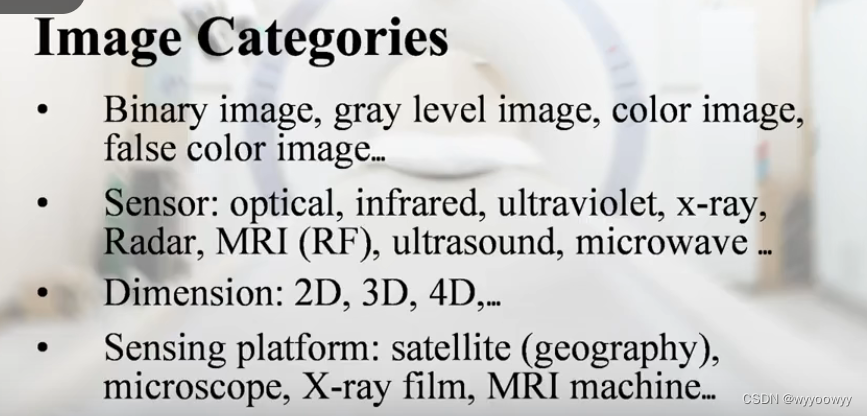

8、医学图像的类别

两个灰度值:比如0/1,0/255

多个灰度值,比如0-255

彩色图像:三个灰度图像的叠加 RGB,三个channel

红外图片,能够很好地表达温度的变化

紫外图片

显微图片

三维扫描

核磁共振图片

超声图像